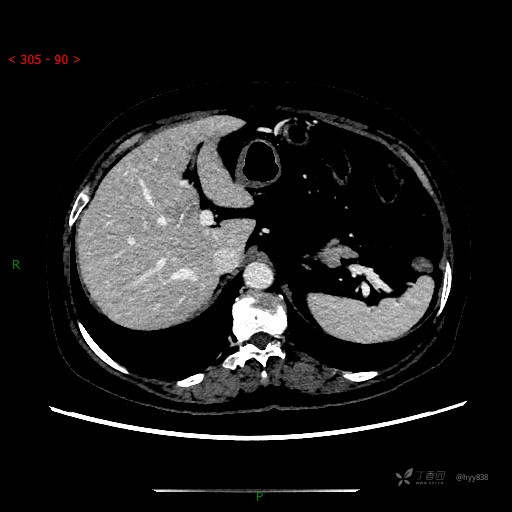

静脉期